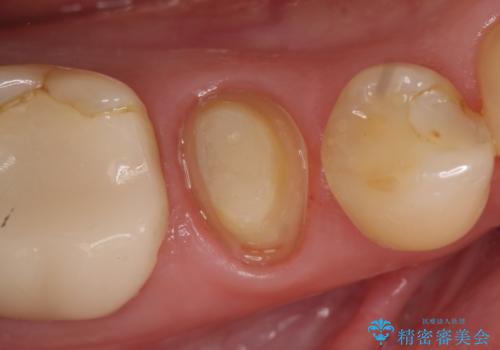

- 右下でものを咬むと痛むので診て欲しいといらっしゃった方の症例です。

検査の結果右下5番目の歯の神経が死んでいたため、根管治療を行った後、オールセラミッククラウンによる補綴を行いました。